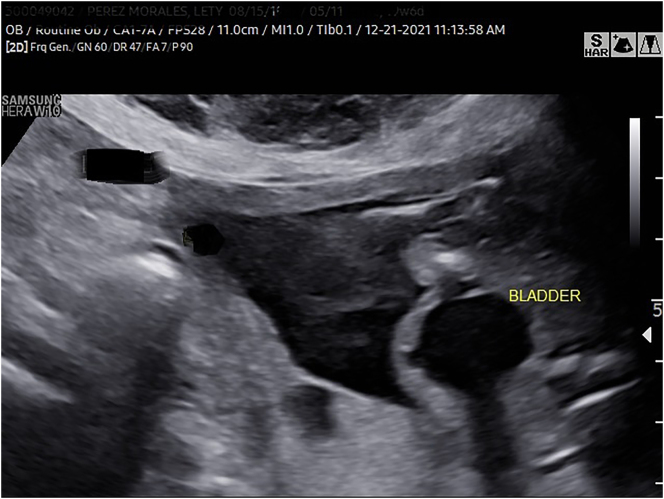

Case presentation: We present two cases of LCCS2, a rare autosomal recessive disorder in the arthrogryposis multiplex spectrum of syndromes whose sine qua non feature is the presence of nonobstructive, neurogenic megacystis. The prenatal diagnosis of this syndrome has not been previously reported. This syndrome has been previously studied in detail in an Israeli-Bedouin kindred but it has not been reported in the Americas.

Abstract Image